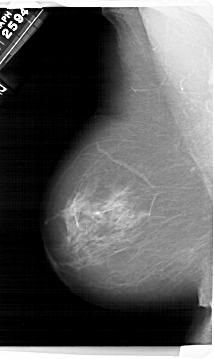

A_1495_1.RIGHT_MLO

RIGHT_MLO LINES 6871 PIXELS_PER_LINE 4186 BITS_PER_PIXEL 12 RESOLUTION 43.5 OVERLAY